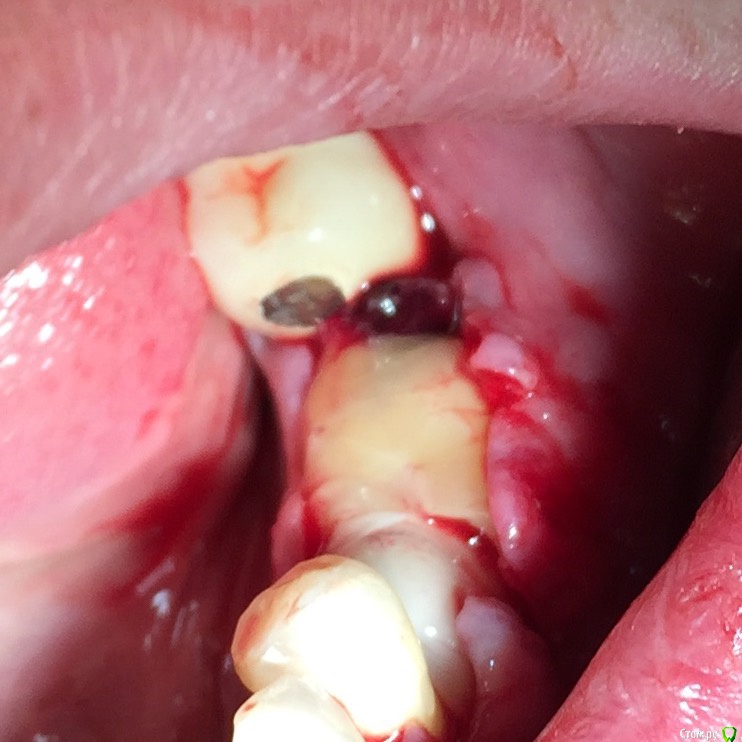

Глеб Митрофанов Опубликовано 12 сентября, 2015 Поделиться Опубликовано 12 сентября, 2015 (изменено) Решил потратить деньги , отложенные на Гамборену , приобрел набор для расщепления . Протестировал , понравилось . Особенно понравился пьезоаппарат , учитывая то , что впервые работал пьезо . За одно протестировал и джейловский гаджет для сбора кости , тоже понравился . Уже по обыкновению использовал A-PRF и I-PRF. Фото с телефона , обрезанные , на телефоне четче смотрятся. Изменено 12 сентября, 2015 пользователем Глеб Митрофанов 4 Ссылка на комментарий

alekszander Опубликовано 12 сентября, 2015 Поделиться Опубликовано 12 сентября, 2015 Прошу прощения, но ушили как то в натяг (по фото) или ошибаюсь? Делали мобилизацию лоскута? Ну и швы грубовато очень. А так спасибо мне познавательно расщепление посмотреть. 1 Ссылка на комментарий

Глеб Митрофанов Опубликовано 12 сентября, 2015 Автор Поделиться Опубликовано 12 сентября, 2015 Прошу прощения, но ушили как то в натяг (по фото) или ошибаюсь? Делали мобилизацию лоскута? Ну и швы грубовато очень. А так спасибо мне познавательно расщепление посмотреть. Мобилизация была, лоскут свободно перекрыл поле , швы двумя этажами , матрацные выворачивают края , поэтому вид грубости создаётся . 1 1 Ссылка на комментарий